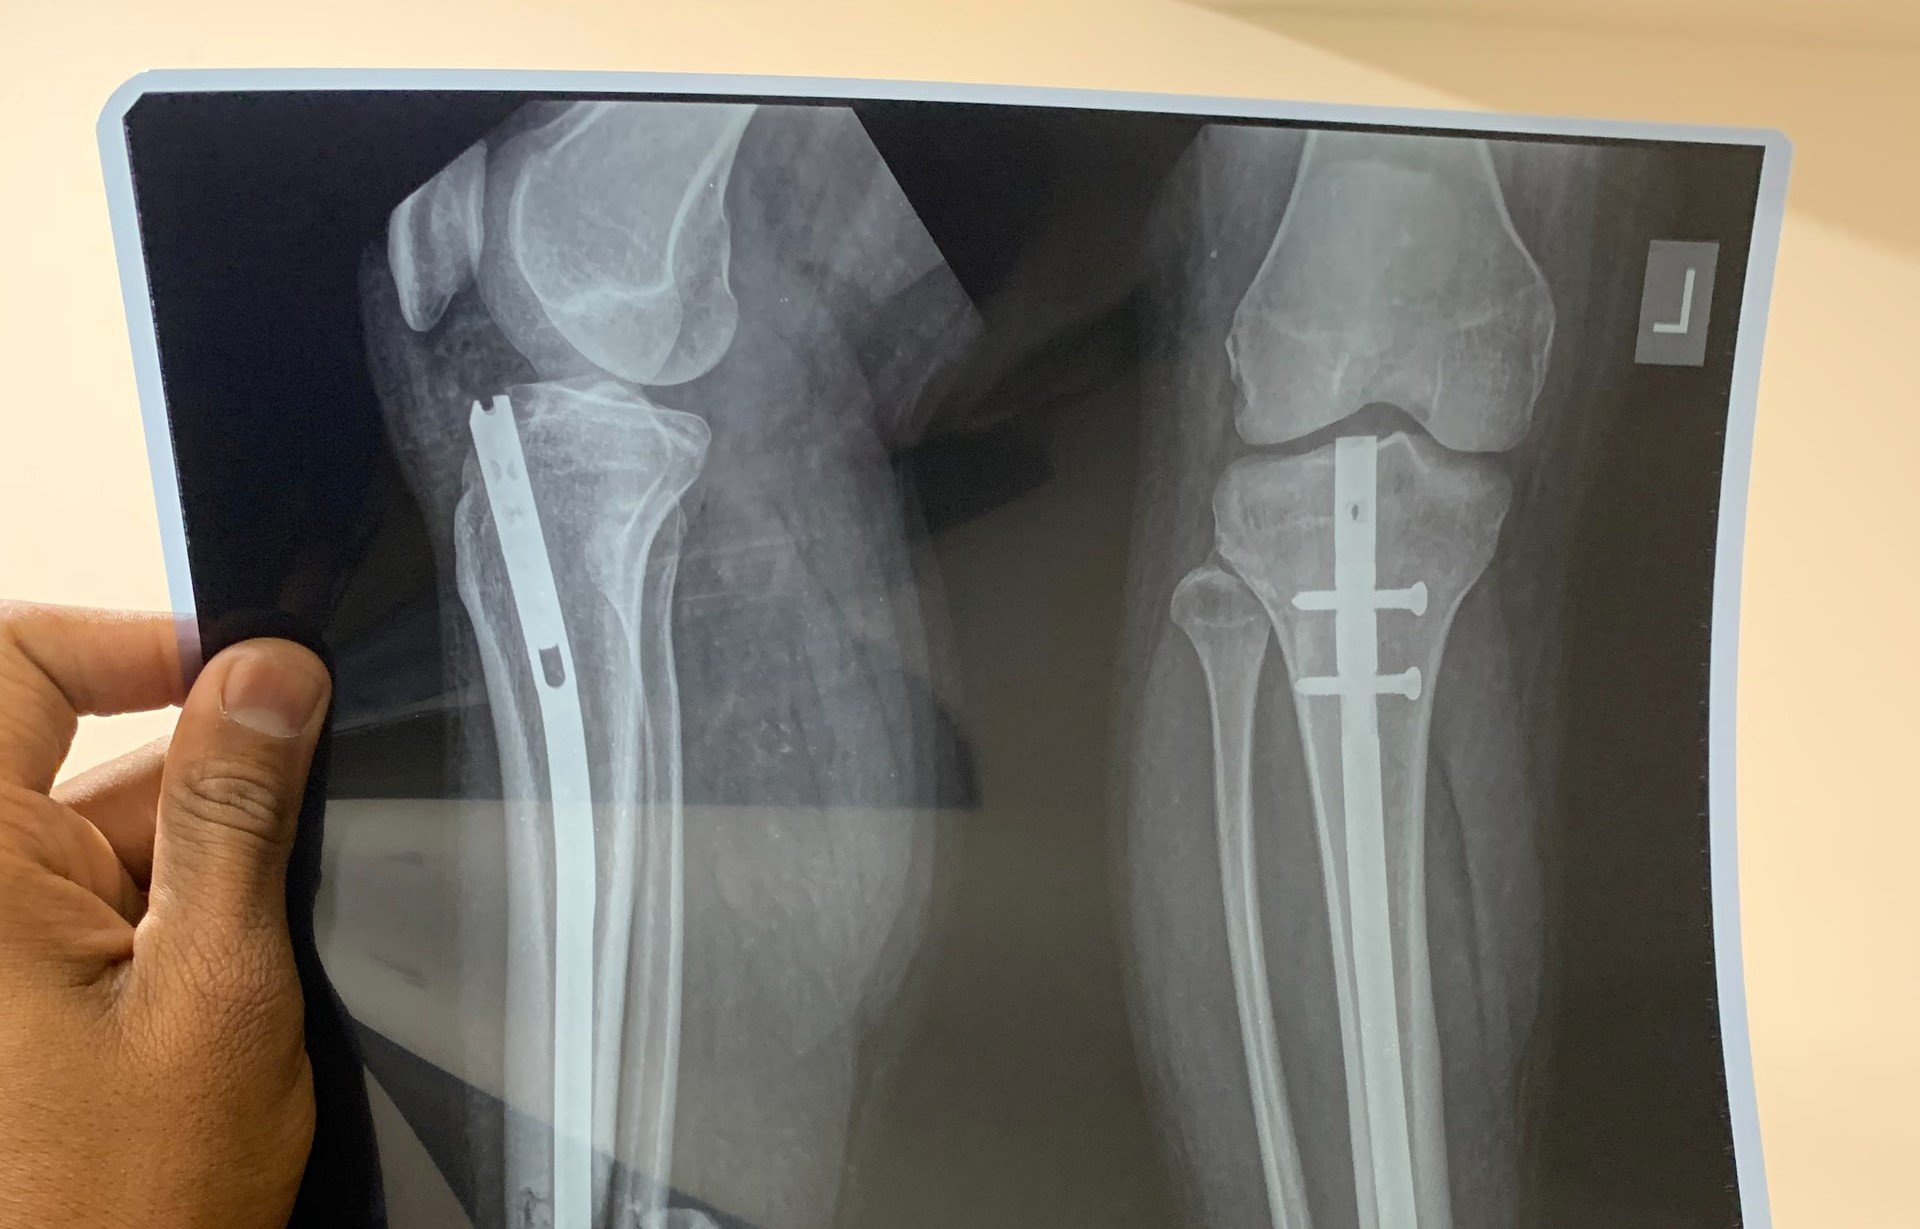

Weitere Teilnehmer der mutmaßlichen illegalen Spielrunde seien mithilfe von Leitern auf die Dächer umliegender Häuser geflüchtet, um sich dem Zugriff der Beamten zu entziehen. Einer von ihnen habe sodann versucht, sich mit einem Sprung von einer Mauer vor der Polizei in Sicherheit zu bringen. Dabei habe er sich eine schwere Verletzung am Bein zugezogen. Daraufhin habe er ins Krankenhaus eingeliefert werden müssen.